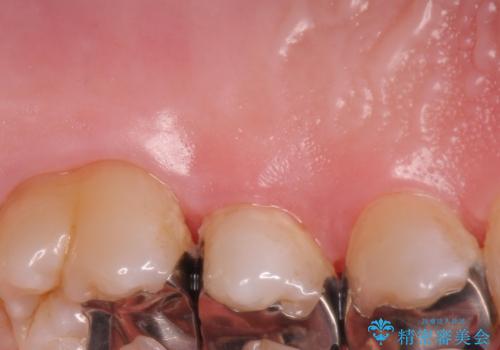

歯根の分岐部よりも根尖側の頬側面が露出している状態でしたが、露出部位を分岐部までに抑えることができました。

しみる症状も改善され、大変喜んでいただけました。

術後は歯肉が下がらないよう経過を追っていきます。